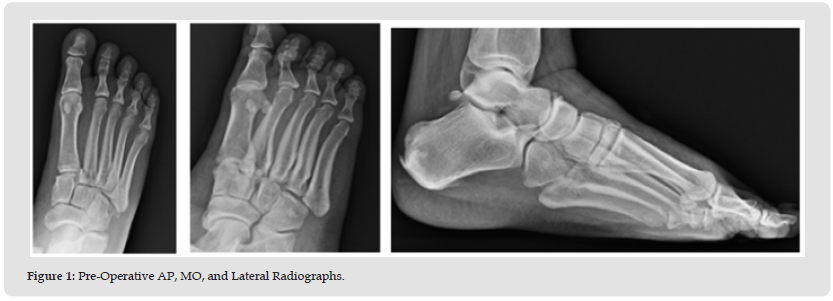

The patient is a 34-year-old morbidly obese female (height 65 in, weight 372 lbs., BMI-61) presenting with disabling right foot pain resulting from a fall (stumbling while stepping down off a porch), where she was taken to the ER and received pain medication which the patient claimed did not provide adequate relief. The surgeon saw her the following day, and X-rays showed a comminuted fracture of the second metatarsal base with intra-articular involvement and slight malalignment of the medial cuneiform with the first metatarsal base. There were also comminuted fractures involving the medial cuneiform, lateral cuneiform, and the cuboid bones, consistent with Lisfranc fracture. Other than morbid obesity, the patient history did not reveal any other significant co-morbidities. The risks and benefits of the surgery and length of recovery were discussed at length with the patient and the surgery was scheduled. The surgery consisted of TMT fusion of the first, second, and third TMTJ, and open reduction and internal fixation (ORIF) of the cuboid bone. At all times during the surgery particular care was used to avoid any damage to neurovascular structures. The first TMTJ was prepared by distraction and fenestration to allow for the placement of Catalyst Bone Graft substitute to promote fusion at the site and a Paragon 28 Lisfranc plate (Zimmer Biomet, Warsaw, IN) was inserted over the fusion site with both locking and non-locking screws.

The position and correct placement of the construct was confirmed using fluoroscopy. The second TMTJ joint was prepared using a separate incision however the second metatarsal base was in severe comminution and required a cannulated “home run” screw (provides axial compression across a joint) from the second metatarsal to the medial cuneiform. The medial and intermediate cuneiform surface was prepped for fusion and both Catalyst bone graft and a Paragon 28 Lisfranc plate were again used to secure the construct. The third TMTJ was similarly prepared with Catalyst used to promote fusion at the site. In this case a Paragon 15mm staple was used to complete the construct with adequate compression. The first and second TMTJ fusions were performed through separate incisions with the third using the same incision as the second. A separate incision was made for the ORIF of the cuboid bone where any hematoma or unwanted debris were cleared, the fracture was then reduced and held temporarily with a K-wire until a Paragon 28 cuboid fracture plate was placed on the dorsal aspect of the cuboid and accompanying screws were placed using standard lag technique. Intraoperative fluoroscopy showed adequate reduction and proper placement of all internal fixation. Both deep and subcutaneous wounds were closed, and the patient tolerated the procedure well. The procedure took approximately 3 hours with blood loss of only 100 ml.

After a brief period in PACU the patient was discharged from the hospital and returned home. The patient was followed closely post-operatively. Pain, swelling, and ROM continuously improved at each visit while the patient was NWB. At the two-month follow-up some early consolidation of the bone graft was observed at the TMTJ grafted sites as evidenced on X-ray, with no pain following ROM of the mid-tarsal joint. At this point, the patient was instructed to begin partial weight bearing with her boot and a walker. Narcotic pain medication was no longer needed by the patient and discontinued by 10 weeks. At 12 weeks a CT scan showed bony bridging at the arthrodesis sites along with appropriate reduction of the Lisfranc complex. At 14 weeks the patient had transitioned to weight bearing in a regular shoe and reports no pain on physical examination. From this point the patient will return for follow-up only if needed.

Early bone graft consolidation was noted in this patient as early as 8 weeks post-operatively and was complete as evidenced on CT scan by 12 weeks. The early graft consolidation in this case is both interesting and encouraging. This case sets the stage for further research with long term follow-up using Catalyst Bone Graft for any foot and ankle procedure where bone graft is required for predictable and rapid healing (Figures 1-5).